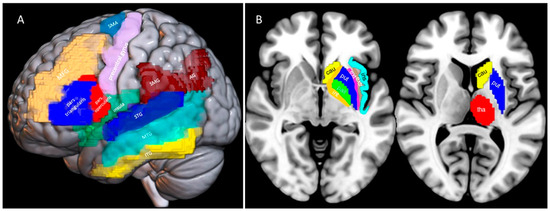

2.2. Neuroimaging Data